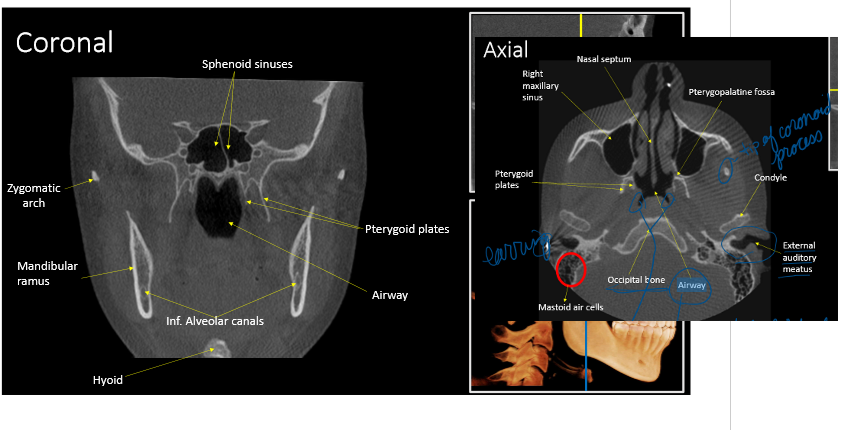

r. max sinus

airway

what is this showing for the CBCT

volumetric rendering

bilateral view of TMJ

What CBCT view is presented, and what type of contrast is shown on the right ?

sagittal; high